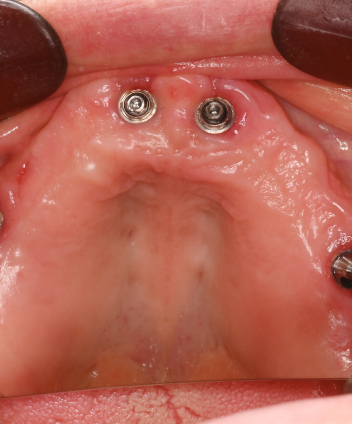

All-on-4(オールオンフォー)は、上顎・下顎に4本ずつのインプラントを埋入し、

その上に全ての人工歯を固定する画期的な治療法です。

従来のように10本以上のインプラントを必要とせず、

骨のある部分を活かして傾斜埋入することで、骨移植なしでも対応できるケースが多いのが特徴です。